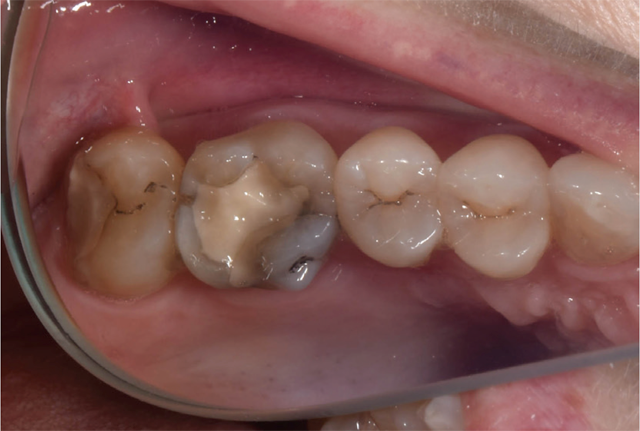

Preparation for full-coverage, all-ceramic onlays for teeth No. 14 and No. 15 was performed using an electric handpiece at 35,000 rpm under copious water irrigation. A bur block designed for all-ceramic preparations was used to achieve an ideal preparation for lithium disilicate. IPS e.max (Ivoclar Vivadent) was selected for its ideal esthetics and strength (Fig. 2).

Fig. 1 Fig. 2